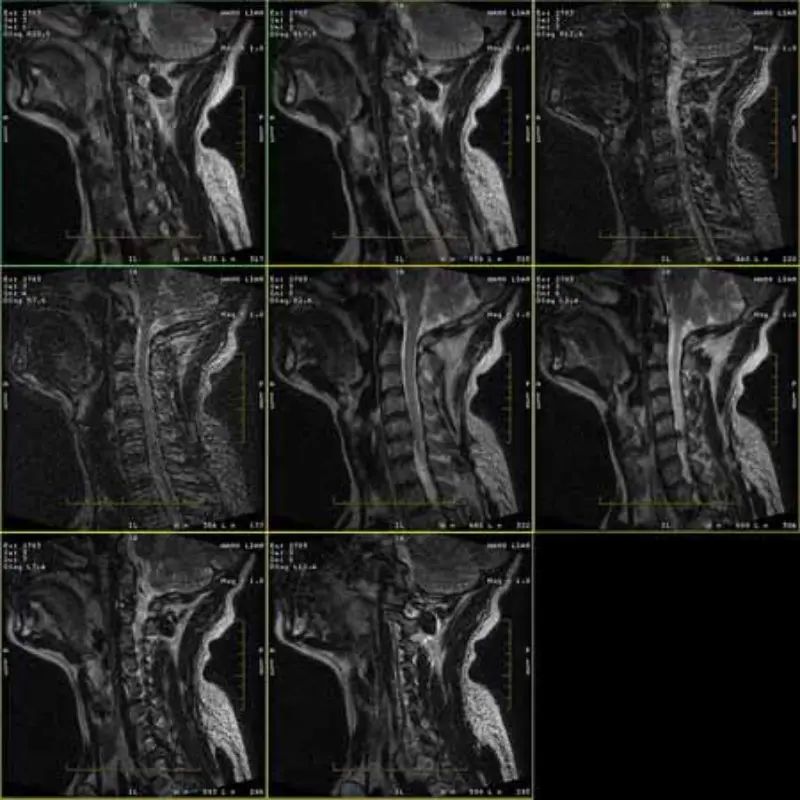

FRFSE 및 GRE 프로토콜의 이미지에는 고스트가 있으며 때로는 낮은 SNR 이미지가 한 시리즈로 나타납니다. 하지만 SE 프로토콜 이미지는 정상입니다.

이미지를 첨부해 보세요.